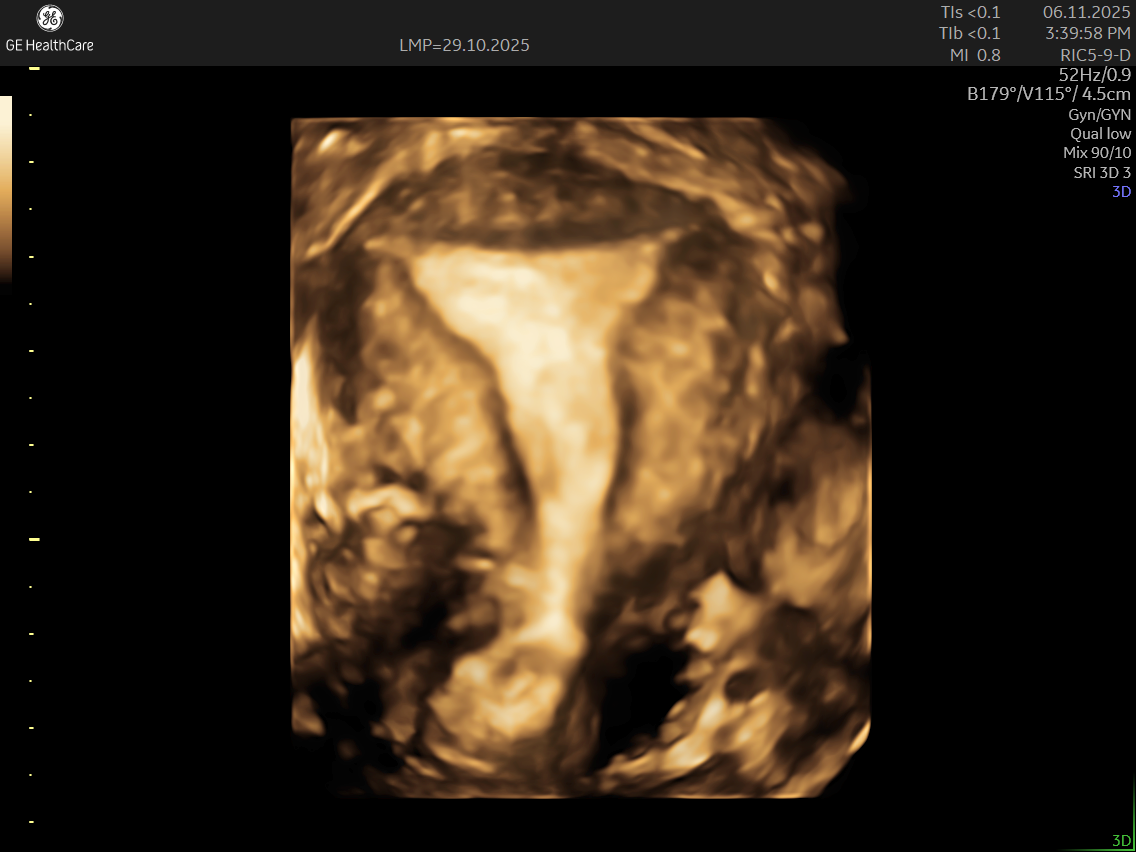

IMAGE GALLERY